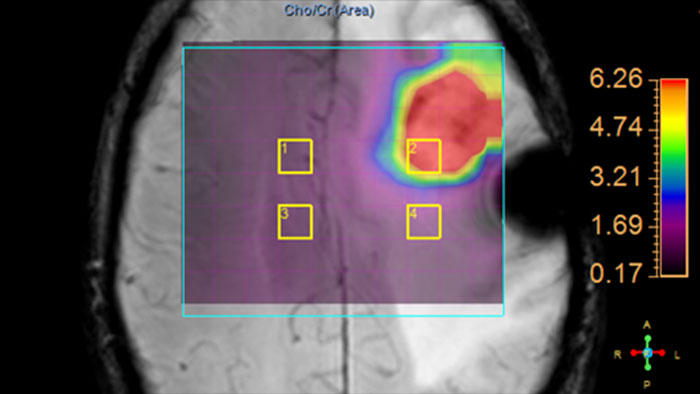

SpectroView

MR SpectroView

Review metabolite maps

MR SpectroView is a task-guided application providing hydrogen single voxel spectra as well as metabolic and ratio maps. It automatically identifies the anatomy to preselect appropriate metabolites or supports user-defined combination of metabolites.

Benefits

• Displays numerical information about metabolites including Peak position and label, SNR, Peak Height, Peak Area, Full Width Half Maximum and Area Ratio of the displayed spectrum.

• Provides metabolite and ratio maps as color overlay on anatomical images or mini spectra on a voxel by voxel basis. Multiple voxels can be selected for spectral comparison.

• Supports automatic and manual phase adjustment as well as a color-coded quality indicator based on field homogeneity and SNR.